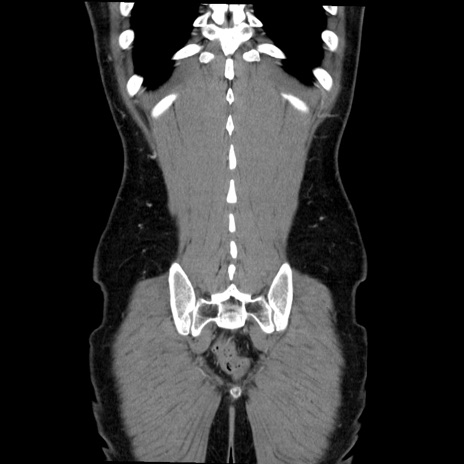

症例36(冠状断像)

【症例】20歳代 男性

【主訴】心窩部痛

【現病歴】今朝より上腹部痛あり。一旦軽快していたが再度出現したため救急要請。昨日夕に白身の魚を含む刺身を食べた。

【身体所見】BP 136/89mmHg、HR 74/min、BT 37.0℃、腹部:膨満、軟、心窩部に圧痛あり。反跳痛なし、筋性防御なし、腸雑音やや亢進あり。

【データ】WBC 17700、CRP 0.48